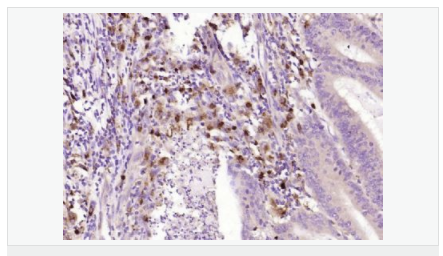

| 產(chǎn)品應(yīng)用 | WB=1:500-2000 ELISA=1:5000-10000 IHC-P=1:100-500 IHC-F=1:100-500 ICC=1:100-500 IF=1:100-500 (石蠟切片需做抗原修復(fù)) not yet tested in other applications. optimal dilutions/concentrations should be determined by the end user. |